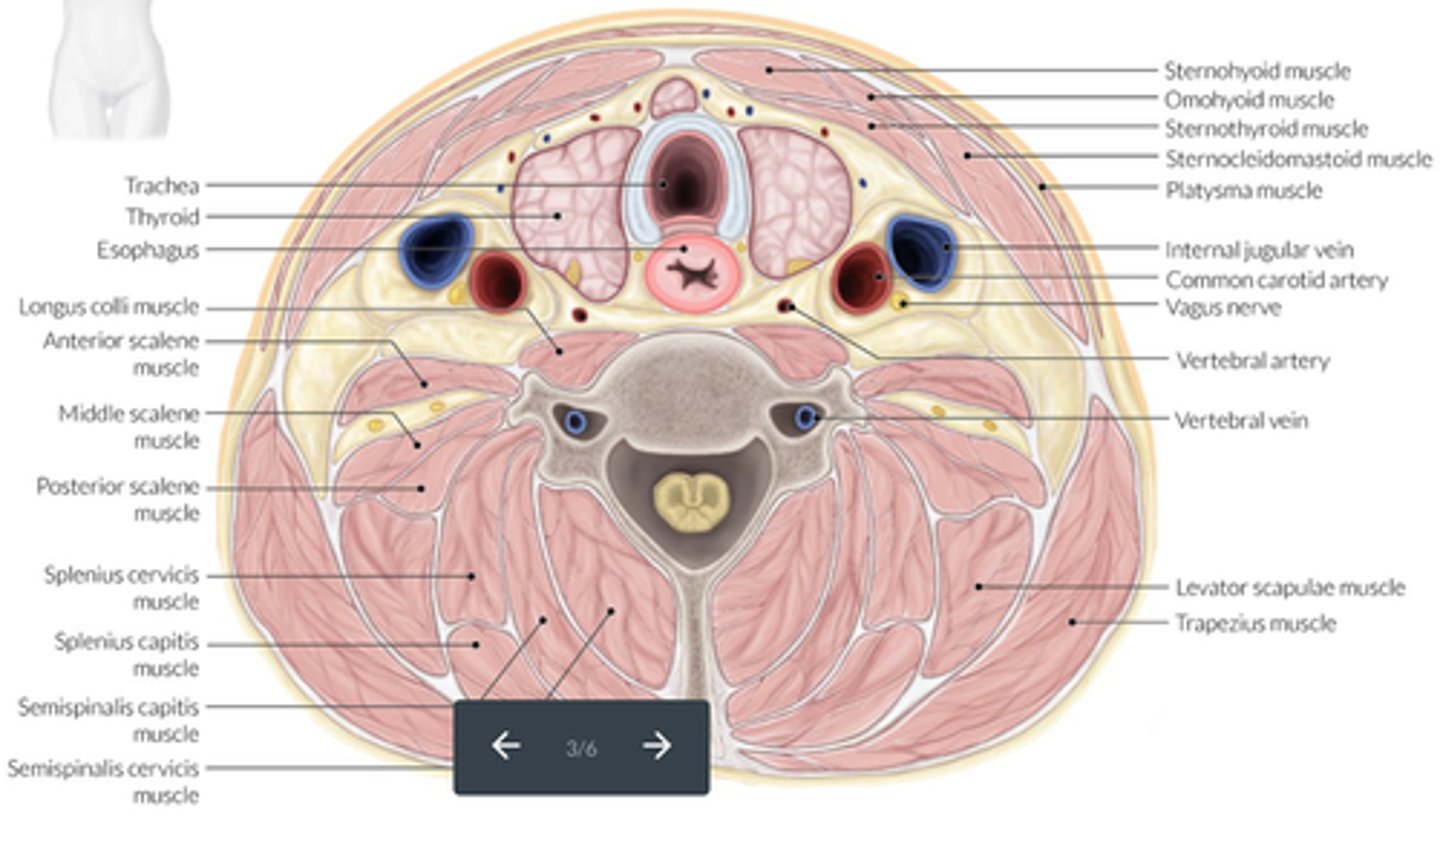

Neck muscles located on the anterior surface of the vertebral column, between the atlas and the 3rd thoracic vertebra; commonly associated with whiplash injuries.

Longus colli muscles

Lateral and superficial neck muscles that attach to the sternum, clavicle, and the mastoid process of the temporal bone; act to flex and rotate the head.

Sternocleidomastoid muscles

A group of long and flat muscles located anterior and lateral to each thyroid lobe; includes the sternohyoid, sternothyroid, and omohyoid muscles.

Strap muscles

What are the 3 strap muscles?

Sternohyoid, sternothyroid, and omohyoid

Muscles of the neck - Longus colli muscles:

-Located on the _____ surface of the vertebral column

-Lie adjacent to the ____ and _____ to the thyroid lobe and CCA

-May be mistaken for an enlarged _____

-Located on the anterior surface of the vertebral column

-Lie adjacent to the trachea and posterior to the thyroid lobe and CCA

-May be mistaken for an enlarged parathyroid gland

Muscles of the neck - Sternocleidomastoid Muscles:

-_____ and _____ neck muscles

-Located _____ to the thyroid lobes, sternohyoid muscle and sternothyroid muscle

-Lateral and superficial neck muscles

-Located lateral to the thyroid lobes, sternohyoid muscle and sternothyroid muscle

Muscles of the neck - Strap Muscles:

-A collective group of long flat neck muscles

-Located _____ and _____ to the thyroid gland

Include the:

-Sternothyroid - located directly _____ to the thyroid gland

-Omohyoid - located _____ to the sternothyroid muscles

-Sternohyoid - located _____ to the sternothyroid muscles

-Located anterior and lateral to the thyroid gland

-Sternothyroid - located directly superficial to the thyroid gland

-Omohyoid - located lateral to the sternothyroid muscles

-Sternohyoid - located anterior to the sternothyroid muscles

Location - Esophagus:

-Located _____ to the left thyroid lobe and _____ to the trachea

Medial

Posterior

Location - Trachea:

-Forms the _____ border of the thyroid glands

Location - Thyroid Lobes:

-_____ and _____ to the corresponding CCA and IJV

-_____ and _____ to the SCM and strap muscles

-_____ to the longus colli muscle

-_____ to the trachea and esophagus

-_____ to the thyroid cartilage of the larynx

-Medial and anterior to the corresponding CCA and IJV

-Posterior and medial to the SCM and strap muscles

-Anterior to the longus colli muscle

-Anterolateral to the trachea and esophagus

-Inferior to the thyroid cartilage of the larynx

Sonographic Appearance:

-Thyroid lobes and isthmus appear as ____geneous solid structures demonstrating a medium-gray echo pattern with a surrounding thin ____echoic line

-Sternocleidomastoid muscle are _____ and oval in shape appearing ____echoic compared with the normal thyroid gland

-Strap muscles are _____ and ____echoic compared with the normal thyroid gland

-Longus colli muscles appear ____echoic compared with the normal thyroid gland

-Thyroid lobes and isthmus appear as homogeneous solid structures demonstrating a medium-gray echo pattern with a surrounding thin hyperechoic line

-Sternocleidomastoid muscle are large and oval in shape appearing hypoechoic compared with the normal thyroid gland

-Strap muscles are thin and hypoechoic compared with the normal thyroid gland

-Longus colli muscles appear hypoechoic compared with the normal thyroid gland